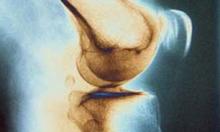

نتایج یک مطالعه جدید تایید کرده که مصرف روزانه برخی از میوهها موجب تسکین درد شدید ناشی از آرتروز زانو میشود.

در مبتلایان به آرتروز زانو مصرف روزانه انگور نه تنها موجب تسکین درد می شود، بلکه انعطاف پذیری را نیز افزایش میدهد.

نتایج مطالعات نشان میدهد، انگور به دلیل دارا بودن خواص آنتی اکسیدانی باعث بهبود فعالیتهای فیزیکی میشود و از دردهای مفاصلی جلوگیری میکند.